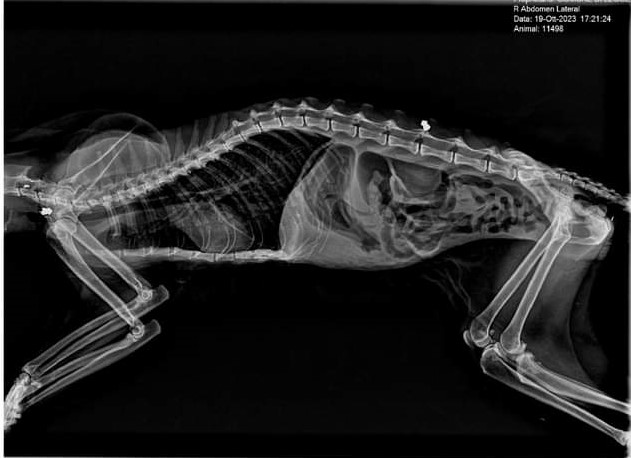

In seguito a una serie di accertamenti e radiografie atte a verificare lo stato di salute generale del felino, i veterinari hanno individuato la presenza di ben due piombini nel corpo della gatta, uno nella regione dorsale e uno nella regione tracheale, quest’ultimo procurava, alla malcapitata, grandi difficoltà nella respirazione.

I veterinari, dopo essersi accertati che, fortunatamente, non erano state colpite zone vitali, hanno provveduto ad estrarre i piombini e a medicare la gatta Bianca che, lentamente, sta riprendendo le forze, riesce a respirare meglio e ad alimentarsi con più facilità anche se è ancora sotto controllo.